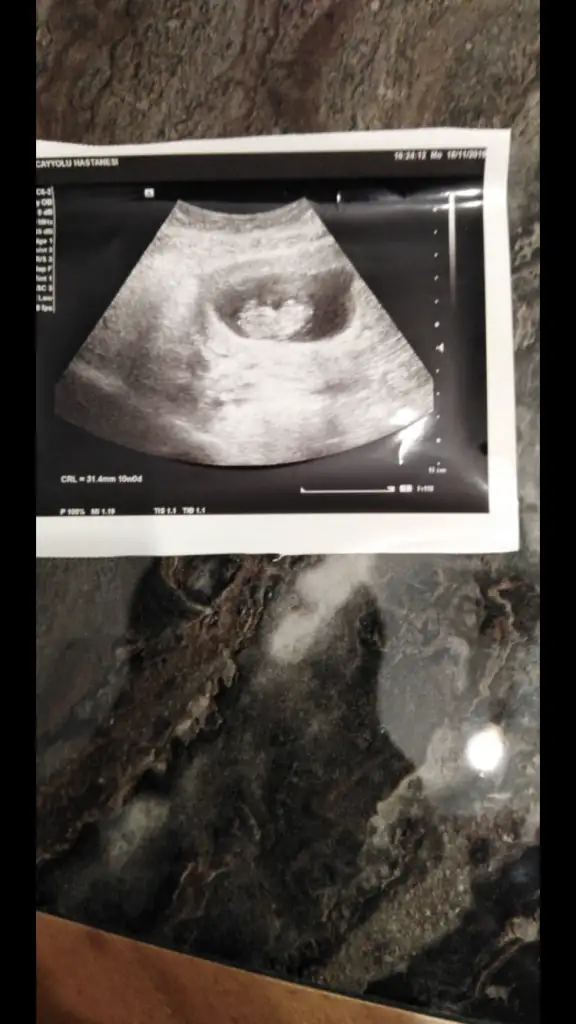

Canlarım ciğerlerimmm nolur vanada yorum yapın çatlicam. Doktor yorum yapmadı. 23. Haftamdayım. Sizce cinsiyet neeeeeee

Buda 11 haftalık görüntüsü arkadaşlar. Tahmimde bulununnnn çatlicamm